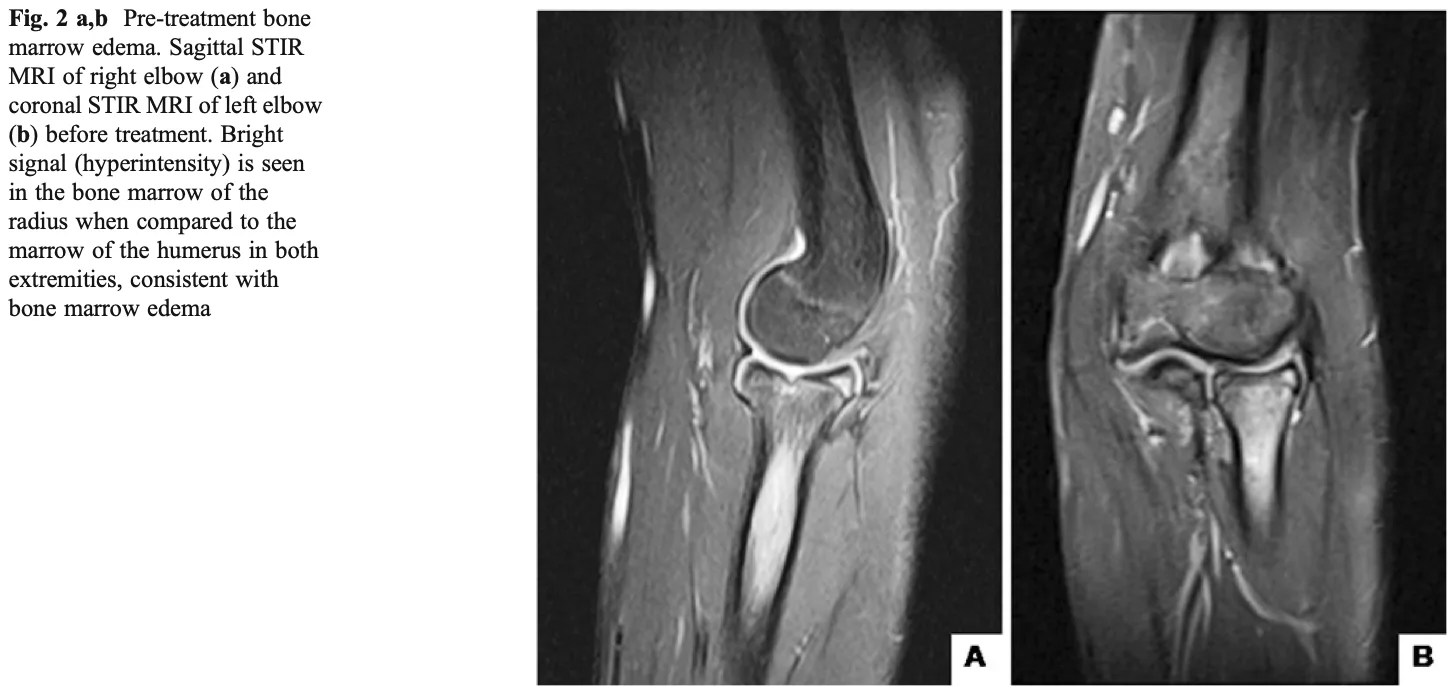

肘の痛みを主訴に, 橈骨の骨腫瘍が疑われる中高年の患者さんが紹介で受診されました. 約3週間前, 椅子から転落して肘を床に強打したとのこと.

肘関節の伸展は痛みで制限され, 回旋動作でも痛みがありました. 持参のCD-Rに肝心の画像データが入っていなかったため, ご了承いただいたうえで当院でX線とCTを撮影.

X線写真では, 骨が透けて見えます(上図).

MRI(右下)では, 骨内は正常な骨髄脂肪しかありません.

X線写真では橈骨結節部(上図の→)が「透けて」見えましたが, CTでは骨破壊などの異常所見は認めませんでした.

橈骨結節は上腕二頭筋腱の付着部で, 構造上X線で薄く写ることがあり, 文献でも“偽囊腫(pseudocyst)”として知られています.

橈骨頚部不全骨折と診断

しかし, 肘関節部の痛みの原因が判らなかったので, MRIも撮像しました.

骨折に伴う出血や浮腫によって頭骨の中が白く変化しています.

MRIでは, 橈骨頭から頚部にかけて骨内に浮腫性変化が見られ、最終的に橈骨頚部の不全骨折と診断しました.